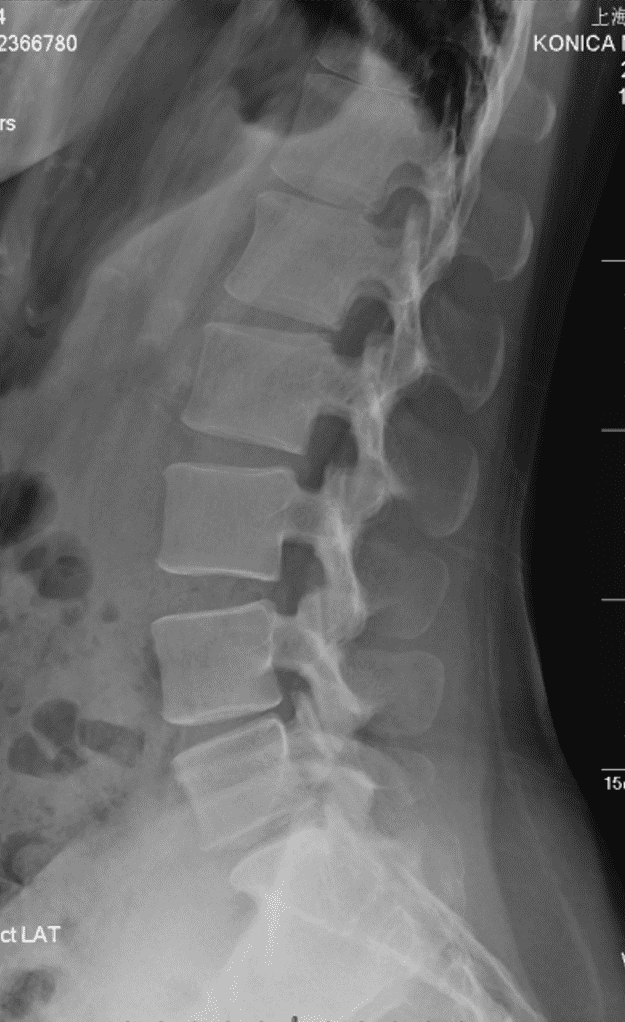

椎骨 / 髂骨 精确标记例

将传统通过点标记训练的 UNet 峰值 22 通道分类模型 + UNet ROI 窗口粗分割模型 替换为对线性顺序和先验顺序更精确的 HRNet 模型,识别率提高并且对于复杂情况的识别能力大幅提升。

将 UNet 训练的髂脊线识别模型(UNet 只适合进行分割,对于线段识别定位预测为概率热图,并不方便进行线段化)替换为 VGG16-BN 专注于线段提取。